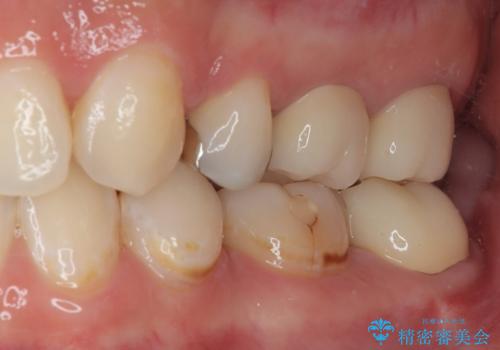

- 左下の奥歯が欠けたとのことで来院された患者様です。検査の結果、埋まっている親知らず抜歯とその手前の左下の7番目の歯のフルジルコニアクラウンによる補綴治療をおこなっていくこととしました。

左下の虫歯が大きいため、神経のテストも行いましたが正常な反応を示しました。

左下の虫歯が歯茎の下にも広がっているので、歯茎の位置を下げるためディスタルウェッジを行い埋伏親知らず抜歯を行いました。また同日に左下の歯を仮歯に変えています。